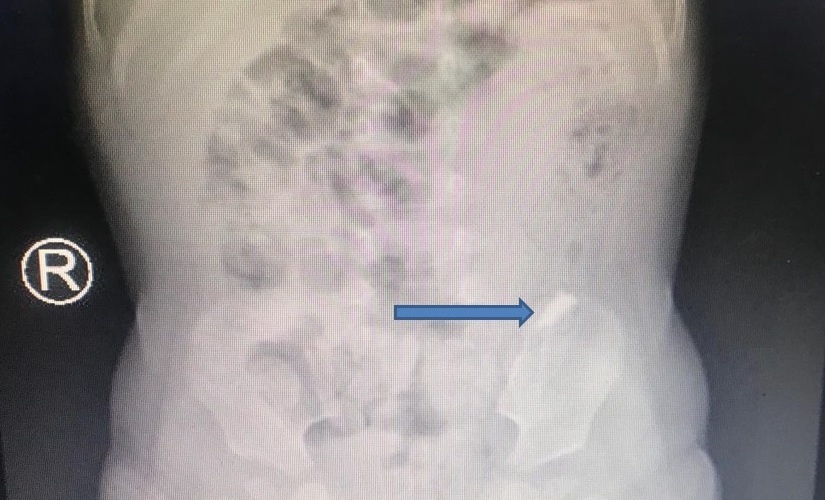

Trên phim X-quang, các bác sĩ ghi nhận mảnh kính di chuyển trên đường tiêu hoá của bệnh nhi, khả năng gắp ra bằng nội soi rất khó.

Dị vật di chuyển trên đường tiêu hoá của bệnh nhi. Ảnh: BSCC.

Kết quả X-quang ngực, bụng cho thấy dị vật đã đi nhanh qua thực quản, dạ dày, môn vị và xuống tá tràng. “Thật khó khăn khi nội soi gắp ra vì nguy cơ gây chảy máu, thủng ruột, dạ dày, thực quản rất cao”, bác sĩ Tiến nói.